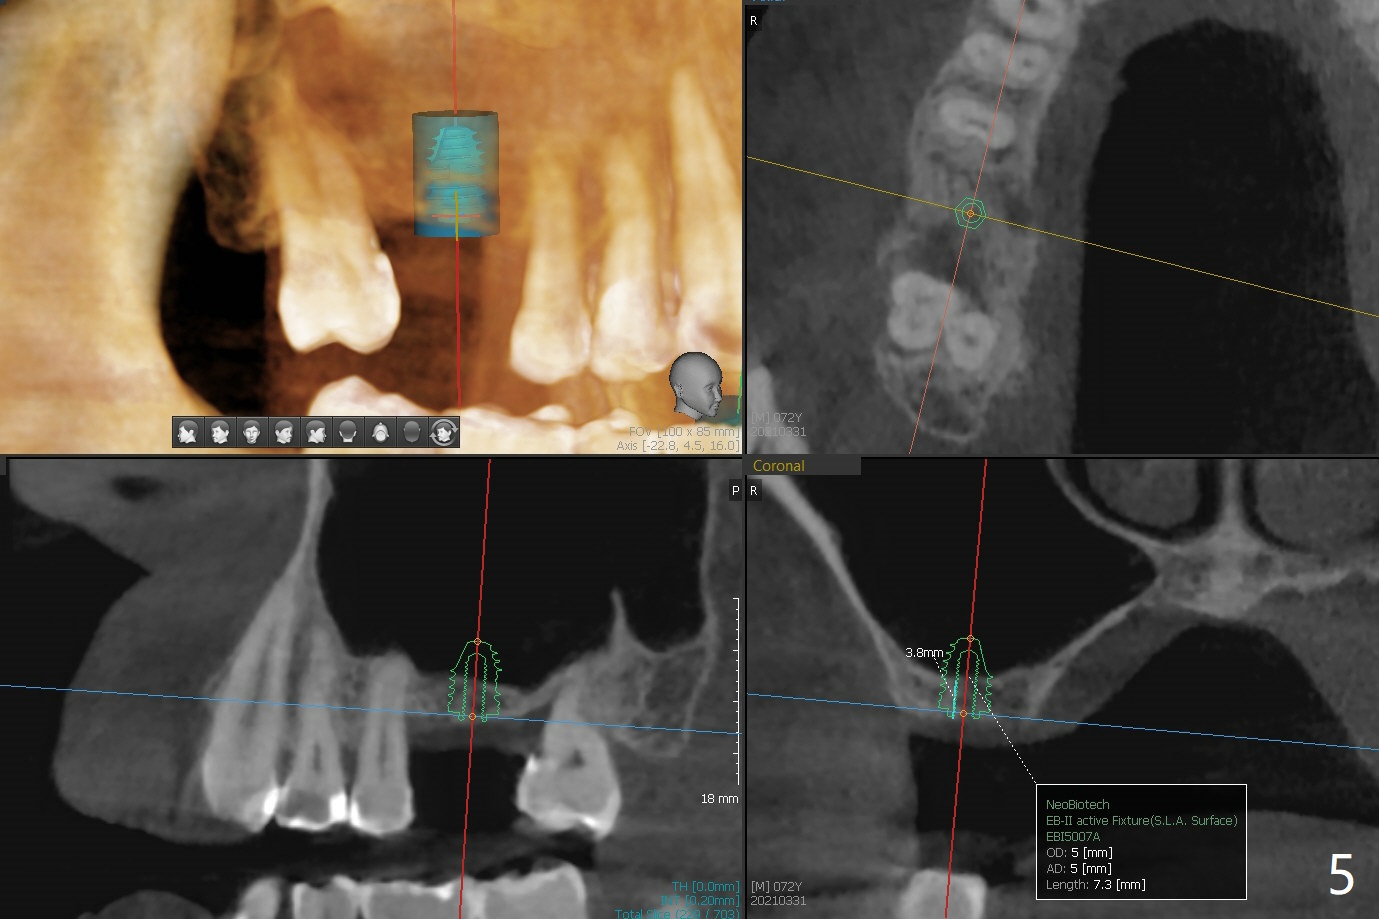

A 72-year-old man agrees to have #14 to be extracted for implant (Fig.1). In the first stage, impression is taken for #14 and 18 implant placement with guide. Due to odontogenic sinus infection (Fig.1,2 *), Z pack will be taken to prevent implant infection associated with sinus lift (Fig.2). Remove provisional and abutment once the sockets heal. To combat #15 supraeruption, the implant at #18 will be placed deep; if the torque is high, place a large diameter healing abutment or provisional with large base will be fabricated so that a short cuffed abutment will be used for final restoration. Heavy occlusal reduction at #15 will be conducted (Fig.3 curved lines). In spite of the fact that the bone height at #3 is 3-4 mm, the sinus floor is flat (Fig.4). Internal sinus lift is not expected to be too difficult. Use Magic Sinus Lifter, followed by implant placement at the same stage (Fig.5,6).